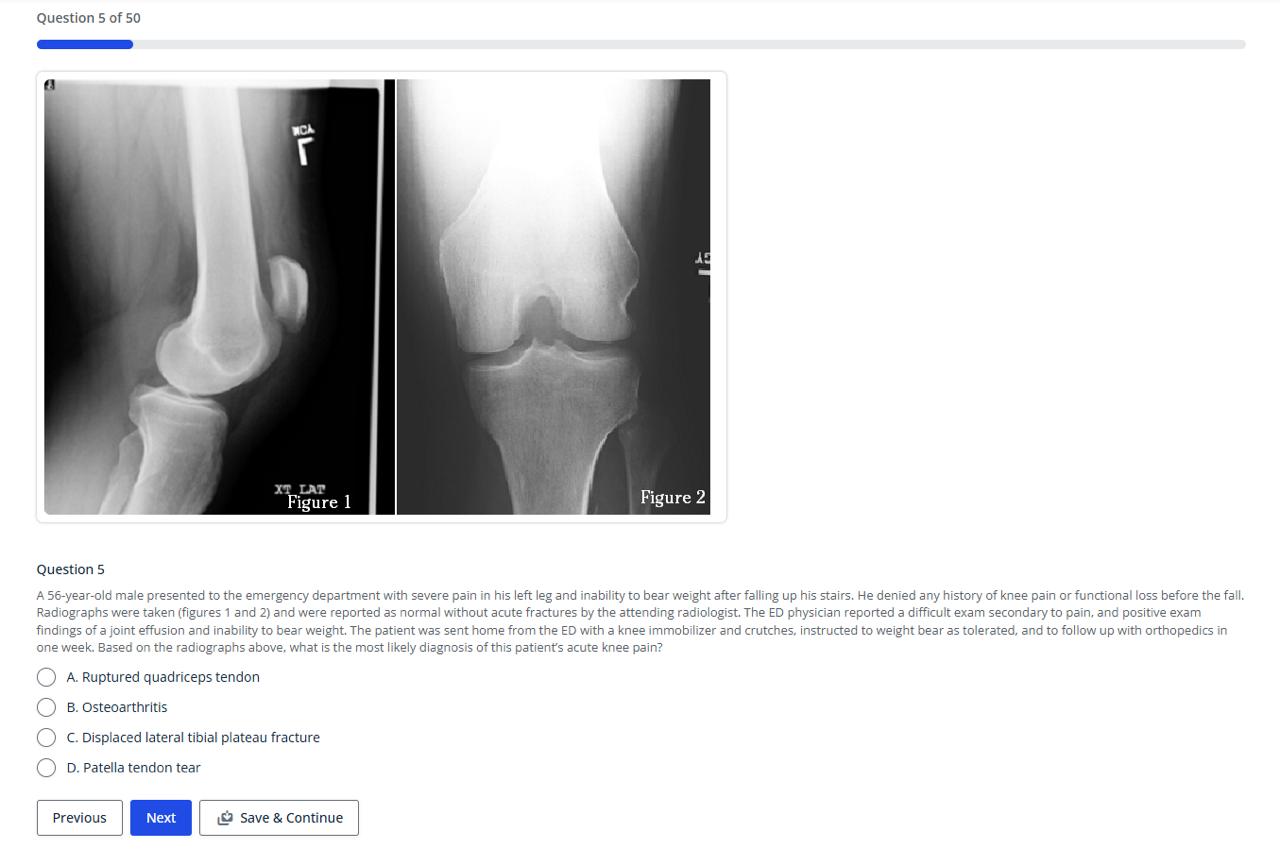

General Orthopedic Exam

(50 questions, 5 Category 1 Self-Assessment CME Credits)

General Orthopedic Exam II

Orthopedic Trauma Exam

(54 questions, 5 Category 1 Self-Assessment CME Credits)

Orthopedic Urgent Care 2

(48 Questions, 5 Category 1 Self-Assessment CME Credits)